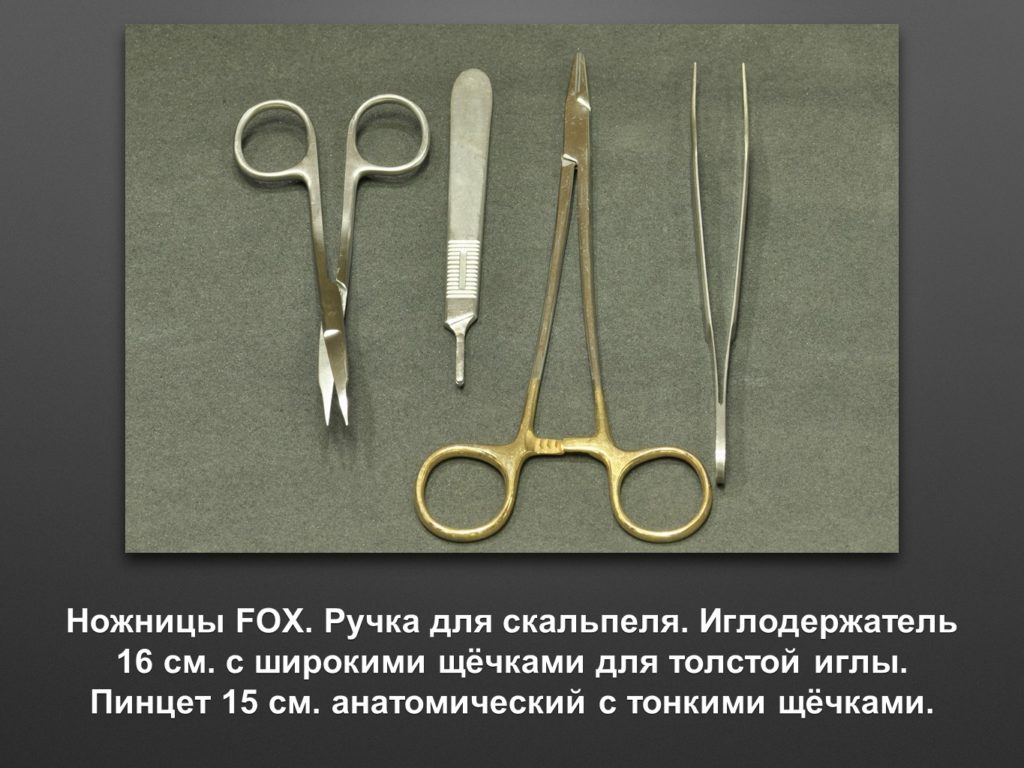

"Выстраданные" наборы инструментов

Все ниже перечисленные инструменты можно приобрести на сайте kohlermed.ru или связаться с нашим менеджером по тел 499-5179401

Все ниже перечисленные инструменты можно приобрести на сайте kohlermed.ru или связаться с нашим менеджером по тел 499-5179401